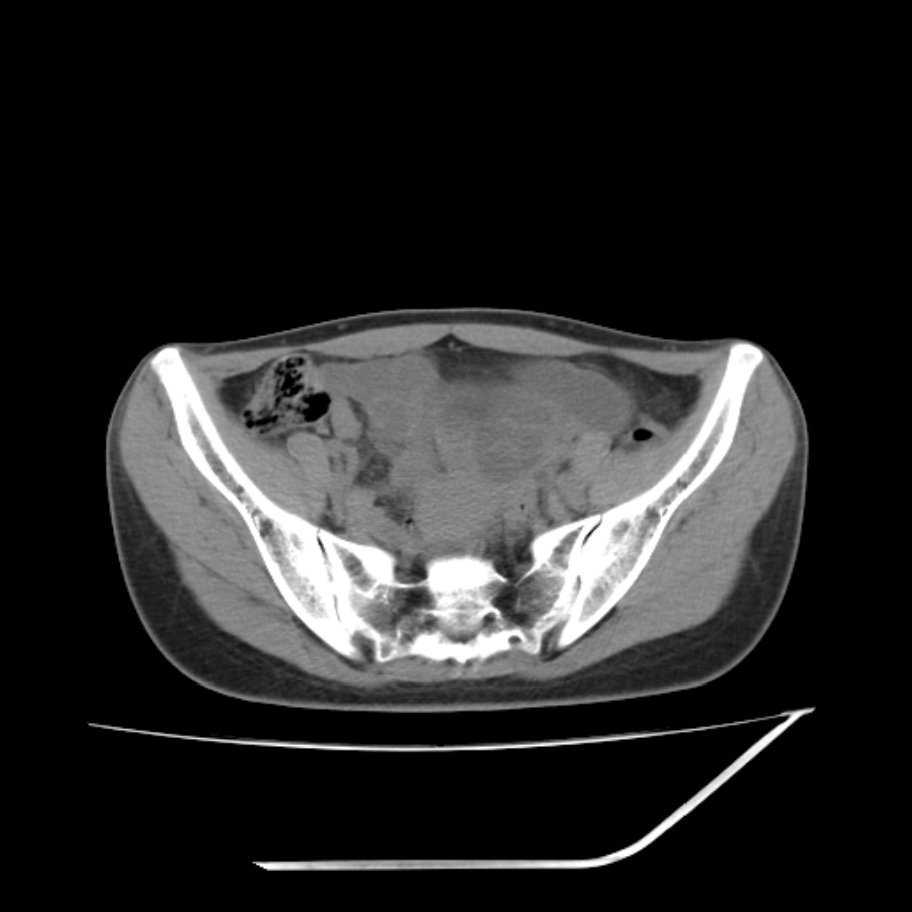

女,25岁。偶尔有右下腹不适感,余无明显异常。(结婚半年),囊壁较厚,是卵巢囊肿吗?

右侧卵巢区椭圆形囊性肿物,内壁光滑 无分隔。直肠子宫间隙内有少量积液征象。结合临床考虑卵巢巧克力囊肿,还要问问有没有痛经,本例ct怎么没有灌肠?要是灌肠或前一前口服造影剂,起码可以和肠管区别开

b超示:囊实性占位,畸胎瘤?临床有痛经。

考虑右侧卵巢囊性占位性病变(巧克力囊肿?),盆腔积液有不排除宫外孕可能,请结合临床和b超。